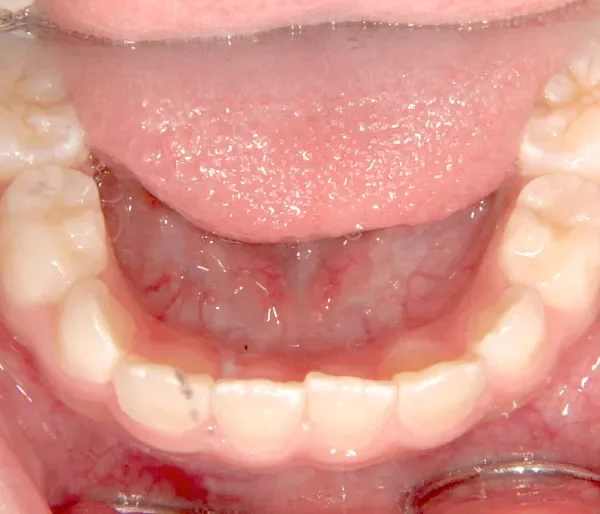

【子供の矯正(一期)】叢生・開咬・前歯で噛めない・舌癖・7歳女児【M.O様】

初診時年齢 小学校1年生 (女性) 主訴 前歯で噛めない

診断名 叢生・開咬 装置名

舌の癖によって下の前歯が出て、上の前歯が短いです。

取り外し式の装置で上下の歯並びを拡げて、下の前歯を引っ込めます。

初診